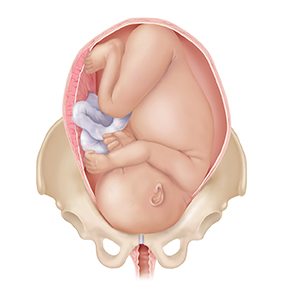

A baby (the fetus) often moves down between the pelvic bones (descend) before birth. If this is your first pregnancy, this may happen 2 to 4 weeks before labor. With repeat pregnancies, the baby may not “drop” until labor begins. The baby usually moves down headfirst. If your baby is not in a safe position for birth, or if there is a problem with the placenta, you may need special care. A cesarean section delivery may be needed.

Breech position.Baby is positioned with feet or buttocks first.